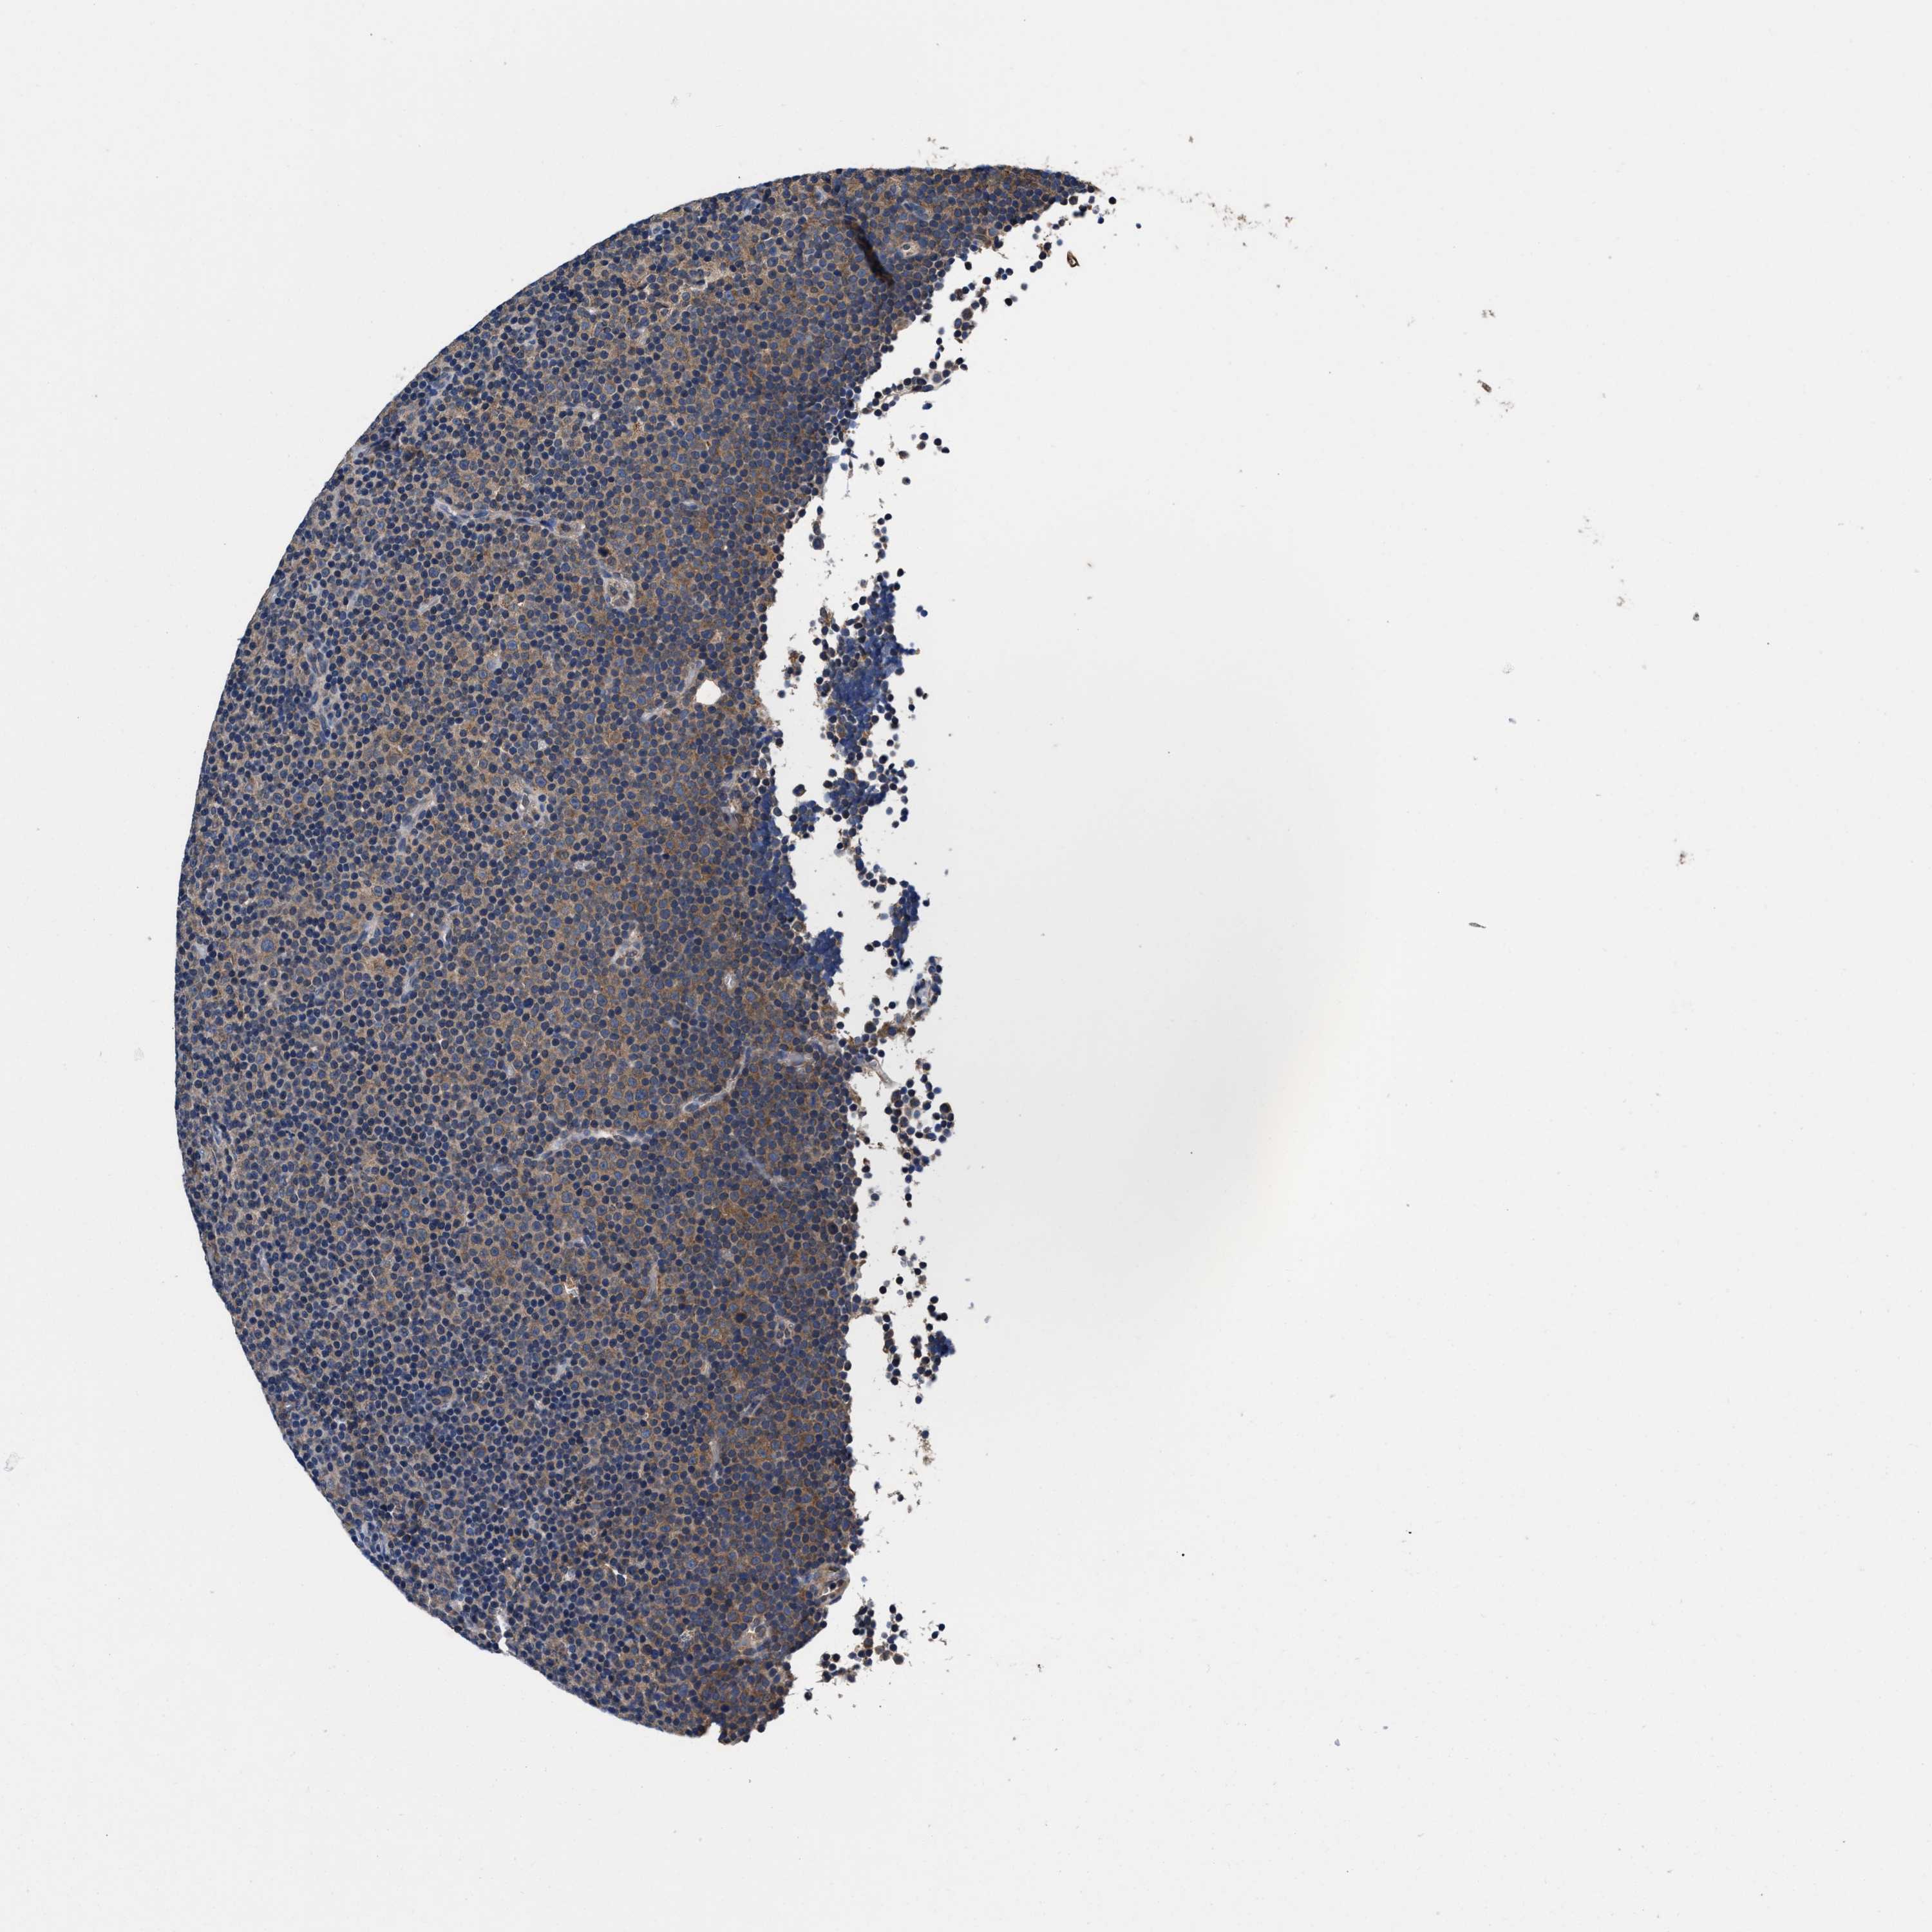

CANCER LYMPHOMA Show tissue menu

LYMPHOMA - Protein expressioni

A mouse-over function shows sample information and annotation data. Click on an image to view it in a full screen mode. Samples can be filtered based on level of antibody staining by selecting one or several of the following categories: high, medium, low and not detected. The assay and annotation is described here.

Antibody stainingi

Antibody staining in the annotated cell types in the current human tissue is reported as not detected, low, medium, or high, based on conventional immunohistochemistry profiling in selected tissues. This score is based on the combination of the staining intensity and fraction of stained cells.

Each image is clickable and will lead to virtual microscopy that enables deeper exploration of all samples and also displays staining intensity scores, fraction scores and subcellular localization as well as patient and tissue information for each sample.

HPA022434

Staining

High

Intensity

Strong

Quantity

>75%

Location

Nuclear

Hodgkin's disease, NOS

Malignant lymphoma, non-Hodgkin's type, High grade

Malignant lymphoma, non-Hodgkin's type, Low grade